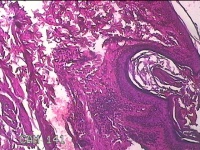

性别

男

年龄

34岁

临床诊断

头部脂肪瘤

一般病史

发现头皮包块2年余。考虑头部脂肪瘤

标本名称

头皮包块

大体所见

灰白粉红色梭形皮肤包块3x2x0.7cm一个,表面糜烂,切面灰白粉红色,质软。